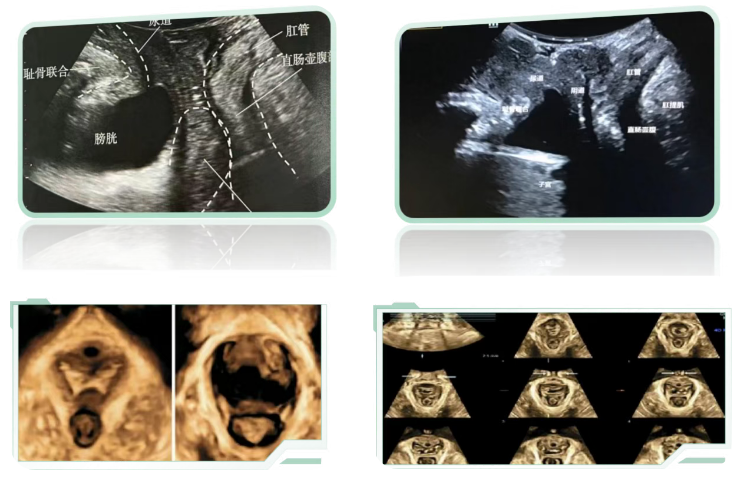

二维模式下,观察静息状态和瓦氏动作(Valsalva maneuver)后盆腔脏器与耻骨联合的相对距离,检查是否有膨出或脱垂。

三维模式下,观察肛提肌是否有撕裂损伤,以及肛提肌裂孔面积是否增大。